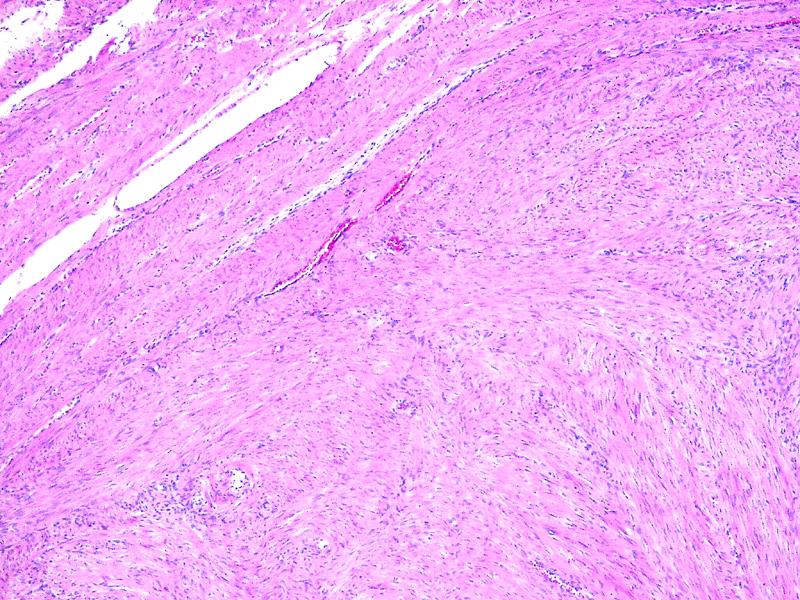

Фибромиома матки: что важно знать о гистологии и лечении